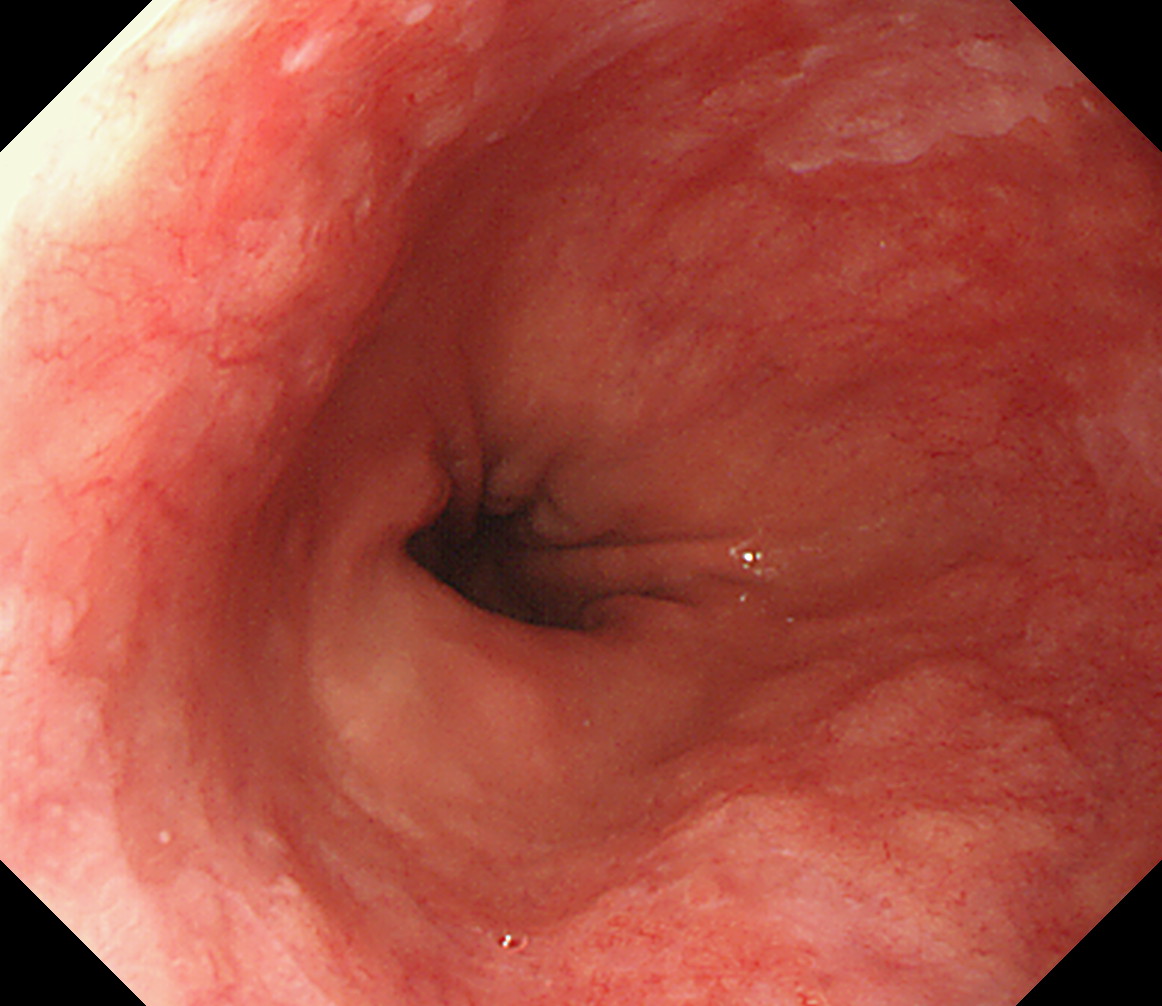

11 胃角部後壁 [見下ろし]になります 中部食道

12 胃角部小弯 [J反転]見上げになります 胃角部後壁